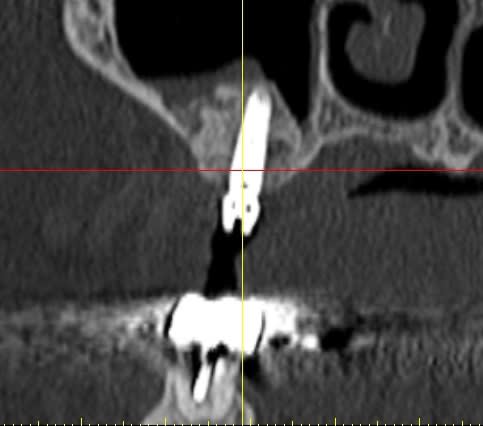

pour votre plaisir mon ami 8 mois d'écarts

fenêtre fermée par du vitalos pas de membrane technique "grosse ouverture"

ce qui ne me plait pas dans ton cas pxav c'est que tu n'as pas décollé la paroi médiale du sinus, tu fais une grosse fenêtre du coup tu te prives d'un apport vasculaire non négligeable.

la demande était radio à J et J+6 mois, pas "présentez un cas de comblement de sinus parfait".

Perso je trouve le résultat "correct" imagine si en plus j'avais fais un CS nickel...

j'ai une préférence pour le mode "ogival" plutôt que "mis à plat", pour des raisons mécaniques, (il me semble que le résultat est meilleur) mais j'ai peut etre tord.

Par contre, l'ouverture réduite ne me gêne pas au contraire, mais dans ce cas là le choix était large.